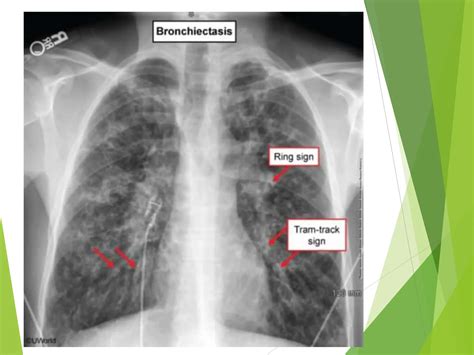

X-Ray Imaging

X-ray imaging is one of the oldest and most widely used diagnosis and imaging techniques. It uses electromagnetic radiation to produce images of the body's internal structures. X-rays are particularly effective for visualizing bones and detecting fractures, as well as identifying certain types of tumors and infections.

Radiation Exposure

Some imaging techniques, such as X-rays and CT scans, use ionizing radiation, which can be harmful if exposure is excessive. Balancing the benefits of these techniques with the risks of radiation exposure is a critical consideration for healthcare providers.